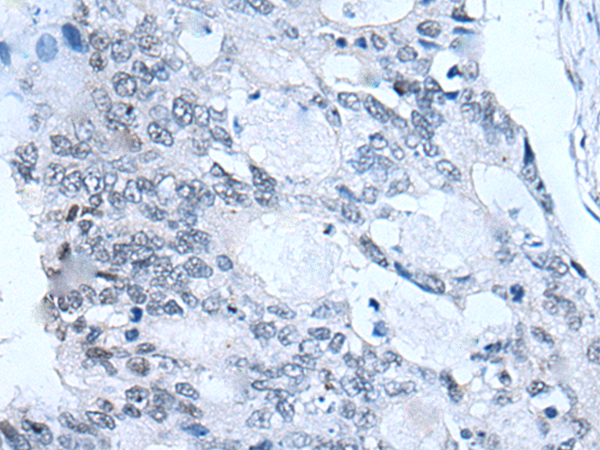

分类: 科研抗体货号: P12706别名: KHL4; DKELCHL应用: IHC反应种属: Human

分类: 科研抗体货号: P12738别名: G2L3应用: IHC反应种属: Human

分类: 科研抗体货号: P12735别名: FOV; CA11; AMP18; BRICD1; foveolin应用: WB,IHC反应种属: Human

分类: 科研抗体货号: P12743别名: HOX3; HOX3B应用: WB,IHC反应种属: Human, Mouse

分类: 科研抗体货号: P12721别名: CNP1应用: WB,IHC反应种属: Human, Rat

分类: 科研抗体货号: P12733别名: GAS应用: IHC反应种属: Human, Mouse, Rat

分类: 科研抗体货号: P12742别名: HOX3; cp19; HOX3E应用: WB,IHC反应种属: Human, Mouse

分类: 科研抗体货号: P12752别名: PYHIN2; IFNGIP1应用: IHC反应种属: Human

分类: 科研抗体货号: P12730别名: HH24应用: WB,IHC反应种属: Human, Mouse, Rat